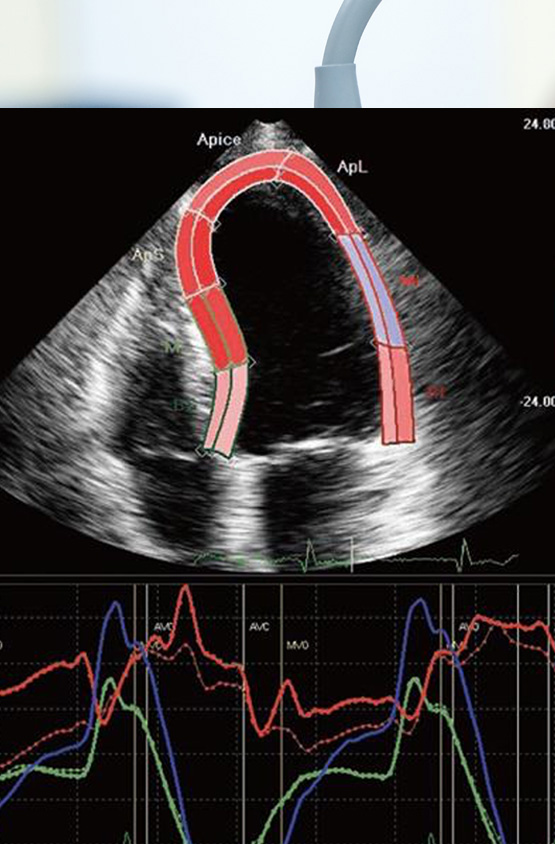

During the procedure: The technician uses the images from the echocardiogram to evaluate heart structures and function. The test may take about 30 to 60 minutes for routine and longer for specialized techniques. Specialized techniques include but are not limited to:In some cases, an ultrasound enhancer called Definity may be used to optimize the images. A bubble study may be ordered for certain indication like a stroke or TIA. Cardia strain analysis is often performed for oncology patients and for certain cardiac conditions such as Amyloidosis.

Measures the deformation of the heart's muscular tissue.

Detect wall motion abnormalities when the images are suboptimal.